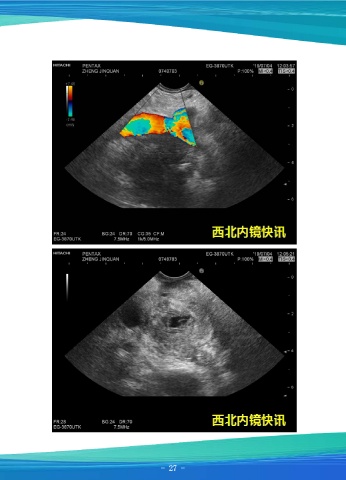

一例胰头占位

患者男,59岁,因“剑突下胀痛5天”就诊,5天前无明显诱因出现上腹部剑突下胀

痛不适,伴刷牙时恶心,与当地医院行腹部增强CT示:胰头部少血供病变,性质考虑为

胰腺癌导致梗阻性胆管扩张,包绕胰十二指肠动脉,十二指肠受侵可能,肝实质内多发

转移,腹膜后散在小淋巴结。于我院行超声内镜检查+穿刺活检,超声内镜示:胰腺钩突

低回声类圆形占位,十二指肠受压,无法通过,病变截面直径约3cm,血供不丰富,但

压迫侵犯肠系膜上静脉,病变质地硬,胰腺体尾部回声大致正常,胆总管未见,但见支

架回声,以25Gproco穿刺针反复穿刺病变,留取细胞及组织样本送检。细胞病理学诊

断示:找到少数癌疑细胞。